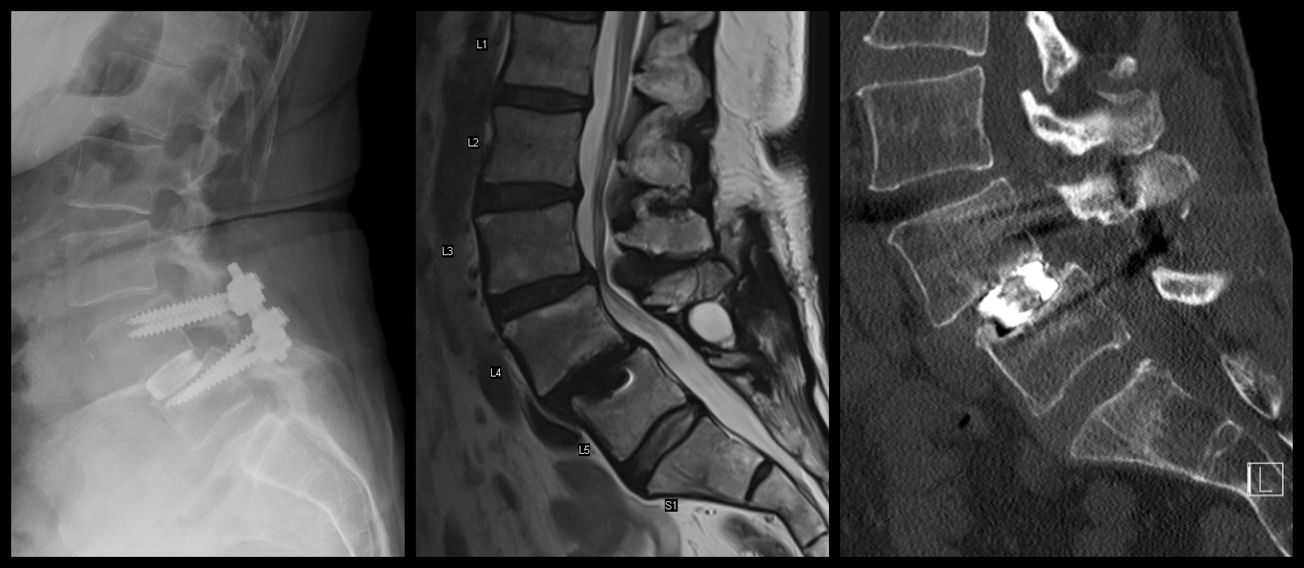

L3-4 TLIF

,

and

Darrel Brodke

October 23, 2020